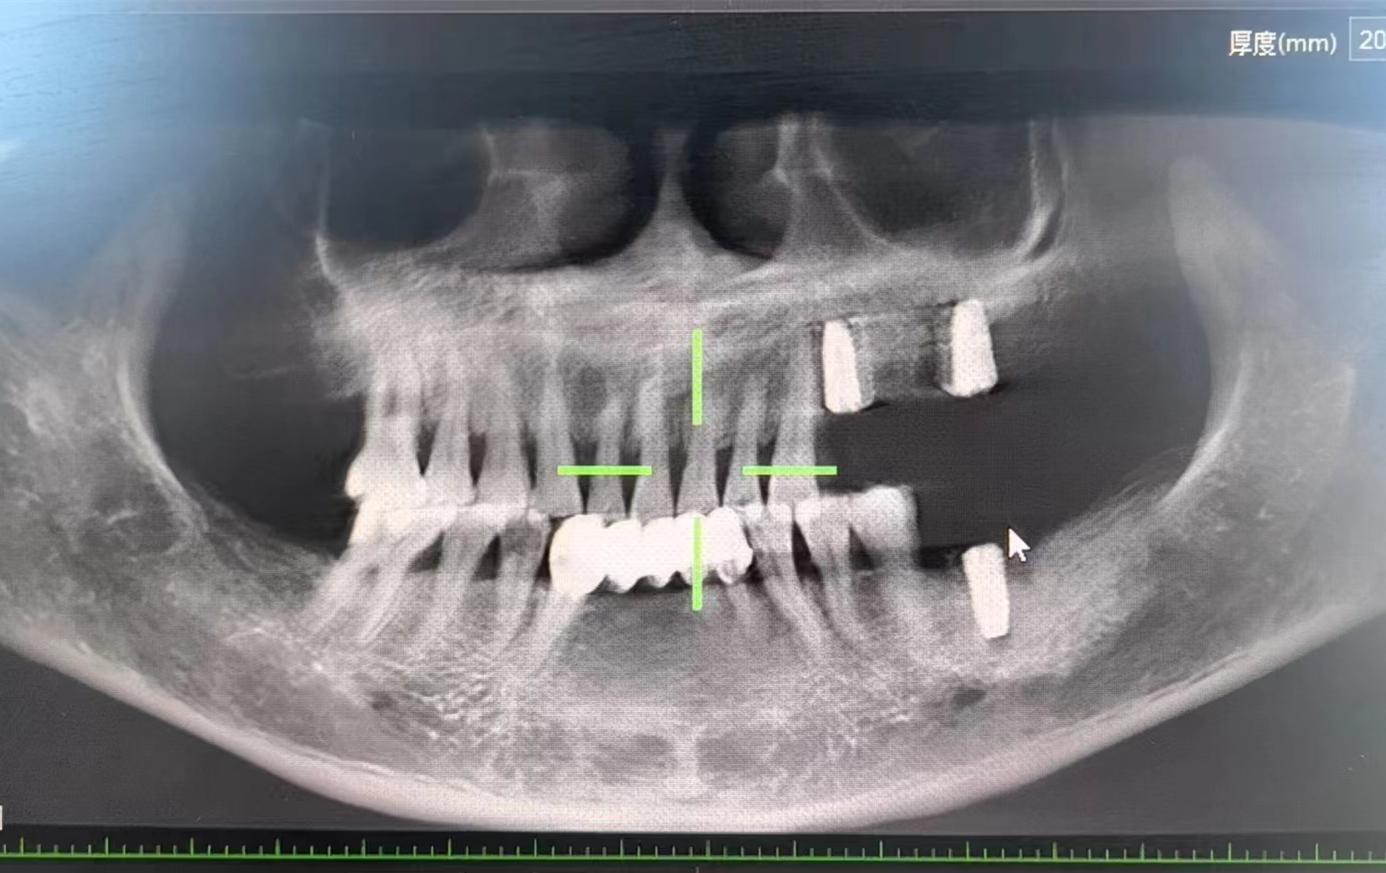

醫(yī)生檢查后,安排患者拍攝口腔CBCT,確定牙槽骨情況,并制定種植計(jì)劃,查血常規(guī),凝血功能,血壓,免疫檢查等。

為了避免患者在炎熱的夏季來回奔波,口腔科高艾玲主任團(tuán)隊(duì)決定為病人一次性種植三顆缺失的牙齒。辛璐醫(yī)生告訴患者,將通過牙科手術(shù)將人工牙根植入牙槽骨內(nèi),然后將牙齦縫合,大約10天左右拆線,之后等待骨愈合后進(jìn)行二期手術(shù)。

通過術(shù)中收集自體骨的形式,滿足了患者不能植人工骨的需求,以有利于患者的方式順利完成手術(shù)。